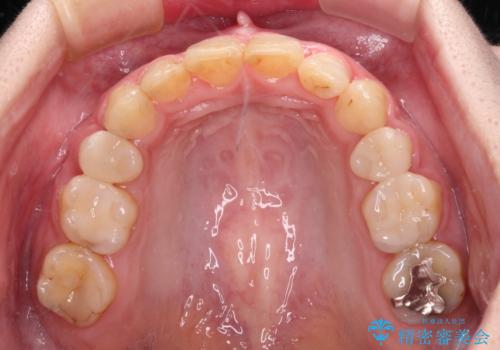

まだ銀歯が残っていますが、大きく目立つ銀歯をセラミックに置き換えることができ、人前で口を開けることを気にしなくなりました。

補綴治療中の後戻り対策をしっかりと行ったことで、歯列全体をきれいに整えることができました。